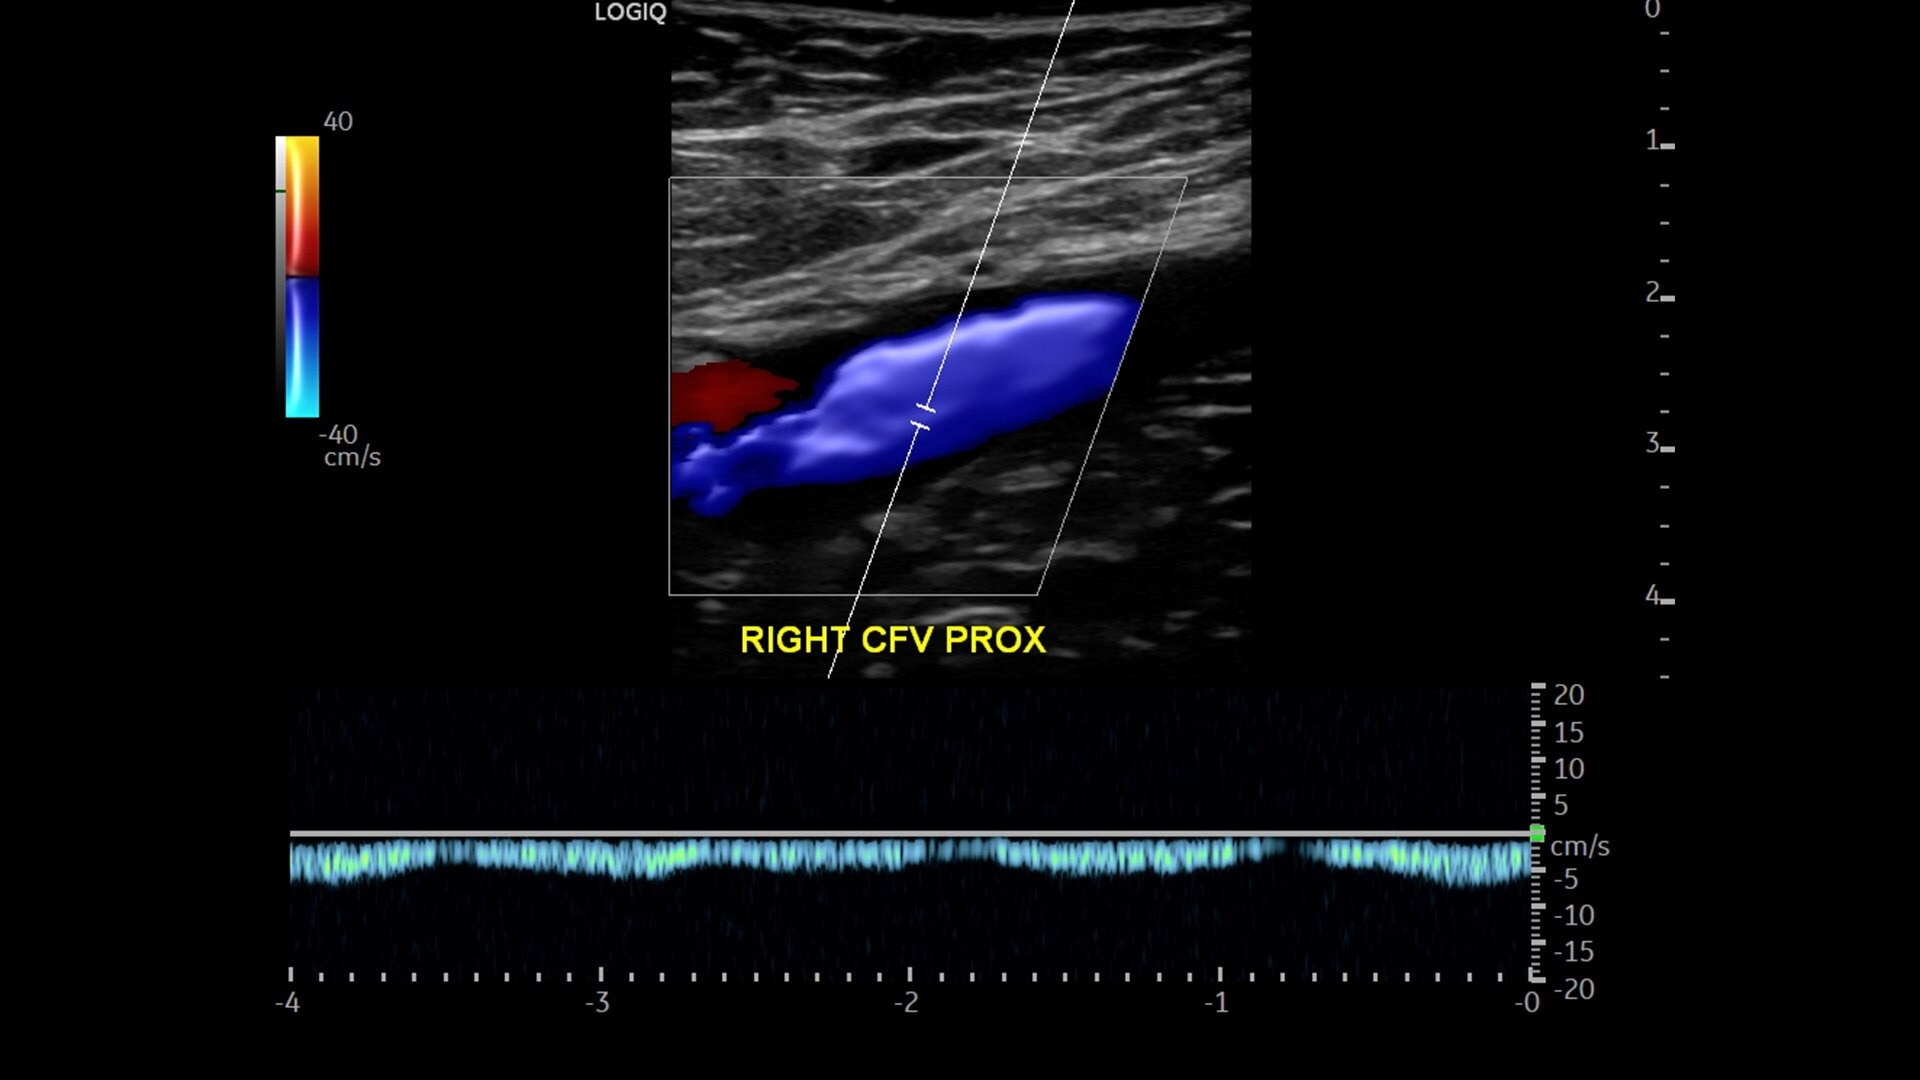

• Advanced flow modes give you the flexibility, from large vessels to fine microvascular detail, to visualize blood flow with precision